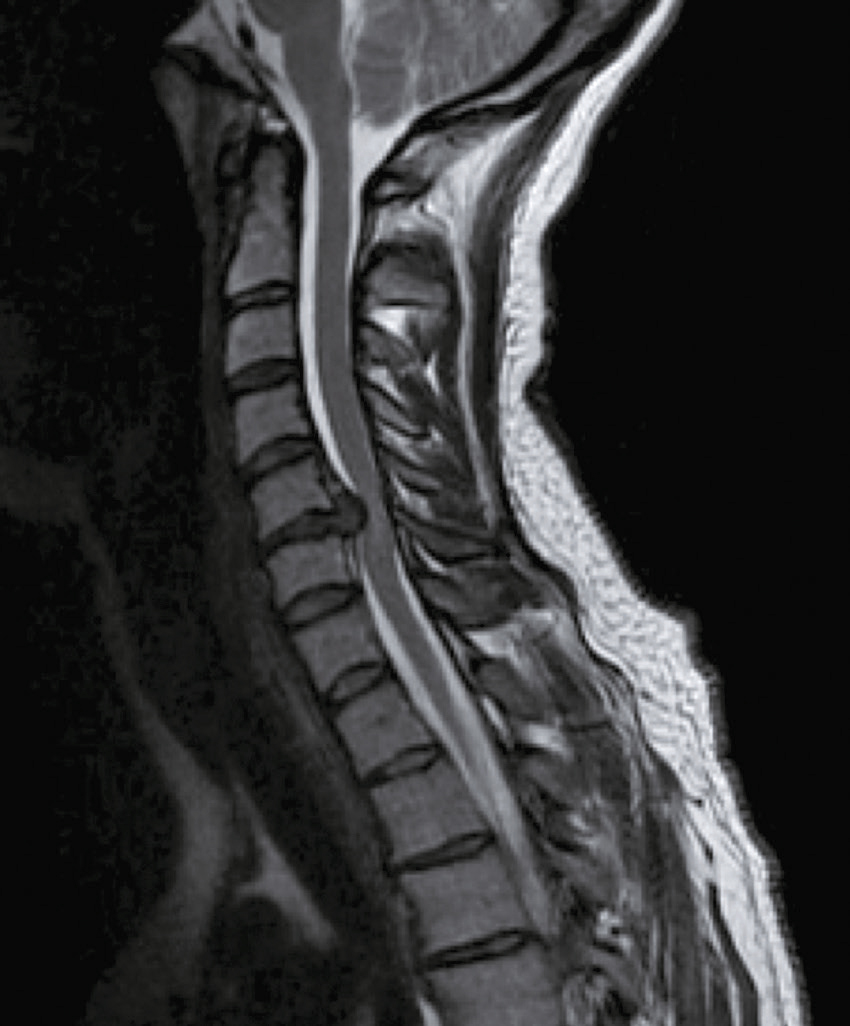

Une IRM médullaire cervicale est réalisée (fig. 31.6). Quelle(s) est (sont) l’(les) affirmation(s) exacte(s) correspondant à cette planche d’IRM ?

L'image montre une IRM de la colonne cervicale. On peut voir les vertèbres cervicales empilées les unes sur les autres, séparées par des disques intervertébraux. L'IRM permet de visualiser les structures internes de la colonne vertébrale, y compris la moelle épinière et les tissus environnants. Les vertèbres apparaissent comme des blocs rectangulaires sombres, tandis que la moelle épinière est visible comme une structure plus claire au centre. Les disques intervertébraux sont les espaces plus sombres entre les vertèbres. Cette image permet de détecter des anomalies telles que des hernies discales, des compressions de la moelle épinière ou d'autres pathologies affectant la fonction neurologique. L'IRM est un outil précieux pour les médecins car elle fournit des images détaillées sans utiliser de rayonnement ionisant. Les images obtenues par IRM sont cruciales pour évaluer l'état de la colonne vertébrale et planifier les interventions médicales nécessaires. Les détails observables, comme la forme et la position des vertèbres et des disques, sont essentiels pour une évaluation approfondie.

- A 584hypersignal extramédullaire à hauteur de C4-C5

- B hypersignal extramédullaire à hauteur de C3-C4

- C hypersignal intramédullaire à hauteur de C3-C4

- D hypersignal intramédullaire à hauteur de C4-C5

- E hypersignal intramédullaire à hauteur de C5-C6

Question 6 – QRM